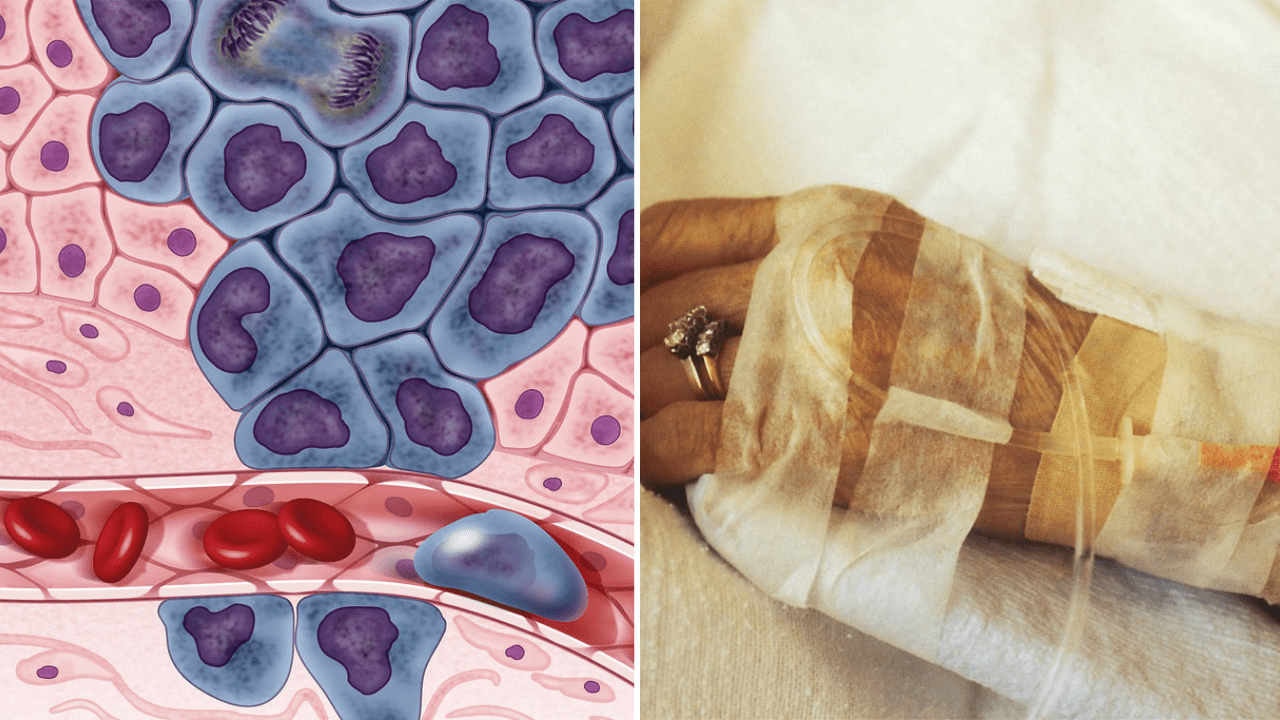

Známa aj ako adjuvantná terapia, je liečebná stratégia, ktorá sa aplikuje po chirurgickom odstránení nádorového tkaniva. Cieľom tejto liečby je eliminovať mikroskopické rakovinové bunky, ktoré mohli zostať v tele po operácii. Tieto bunky sú často príliš malé na to, aby boli viditeľné pomocou súčasných diagnostických metód, no môžu byť zdrojom recidívy ochorenia, ak sa neodstránia.

Monica Avila, onkologička z Moffitt Cancer Center, uvádza, že hoci chemoterapia je často považovaná za agresívnu liečbu, jej preventívna forma je určená len pre pacientov, ktorí už majú diagnostikovanú rakovinu. Chemoterapia sa nikdy nepoužíva na prevenciu rakoviny u zdravých jedincov. Adjuvantná chemoterapia sa zameriava na zvyškové rakovinové bunky, aby sa znížila šanca na opätovný výskyt choroby.

Preventívna chemoterapia je dôležitá preto, že aj po úspešnom chirurgickom odstránení nádorového tkaniva existuje riziko, že v tele zostanú mikroskopické zvyšky rakovinových buniek. Tieto bunky môžu časom prerásť do nových nádorov, ktoré by mohli ohroziť život pacienta. Preto lekári často odporúčajú adjuvantnú chemoterapiu ako spôsob, ako minimalizovať toto riziko.

Dôležité je tiež uvedomiť si, že chemoterapia, či už preventívna alebo liečebná, môže mať závažné vedľajšie účinky. Napríklad vypadávanie vlasov, oslabenie imunitného systému, nevoľnosť, únava a problémy s trávením. Napriek tomu sa mnohí pacienti rozhodnú pre túto liečbu, pretože im poskytuje vyššiu šancu na dlhodobé prežitie.

Niektorí pacienti zažívajú aj dlhodobé následky chemoterapie, ktoré môžu zahŕňať neuropatiu, problémy so srdcom a dokonca aj sekundárne rakoviny spôsobené samotnou liečbou. Z tohto dôvodu je veľmi dôležité, aby pacienti dostali komplexnú podporu a starostlivosť počas celej liečby, a aby boli pravidelne monitorovaní lekármi.

William Dahut, onkológ z Americkej spoločnosti pre rakovinu, vysvetľuje, že chemoterapeutické lieky sú rovnaké, či už sa používajú na liečbu existujúcej rakoviny alebo na prevenciu jej návratu. Pokroky v medicíne však umožnili lepšiu toleranciu týchto liečebných postupov a vedľajšie účinky sú často dočasné.